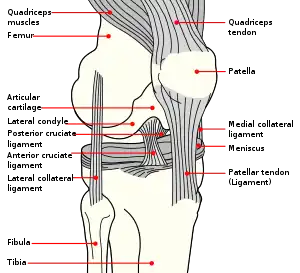

Diagram of the knee | |

The posterior cruciate ligament (PCL) is a ligament in each knee of humans and various other animals. It works as a counterpart to the anterior cruciate ligament (ACL). It connects the posterior intercondylar area of the tibia to the medial condyle of the femur. This configuration allows the PCL to resist forces pushing the tibia posteriorly relative to the femur.

The PCL, ACL, MCL, and LCL are the four main ligaments of the knee in primates.

The PCL is located within the knee joint where it stabilizes the articulating bones, particularly the femur and the tibia, during movement. It originates from the lateral edge of the medial femoral condyle and the roof of the intercondyle notch[2] then stretches, at a posterior and lateral angle, toward the posterior of the tibia just below its articular surface.[3][4][5][6]